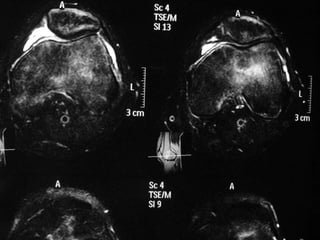

The document presents a detailed case study of a patient with transient osteoporosis of the hip (TOH) and spontaneous osteonecrosis of the knee (SONK) treated at Choithram Hospital & Research Centre in India. Over 20 years, the patient experienced multiple episodes of TOH and SONK with no history of trauma or co-morbidities, resulting in resolutions and recurrences of conditions. The information is intended for orthopedic surgery students and highlights personal experiences and case collections, with a disclaimer regarding content usage and potential controversies.